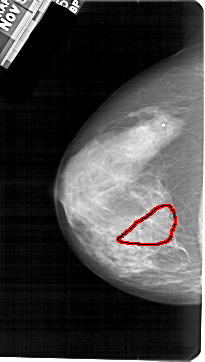

A_1605_1.RIGHT_CC

FILE: A_1605_1.RIGHT_CC.OVERLAY

TOTAL_ABNORMALITIES 1

ABNORMALITY 1

LESION_TYPE CALCIFICATION TYPE PLEOMORPHIC DISTRIBUTION SEGMENTAL

ASSESSMENT 4

SUBTLETY 3

PATHOLOGY BENIGN

TOTAL_OUTLINES 1

BOUNDARY